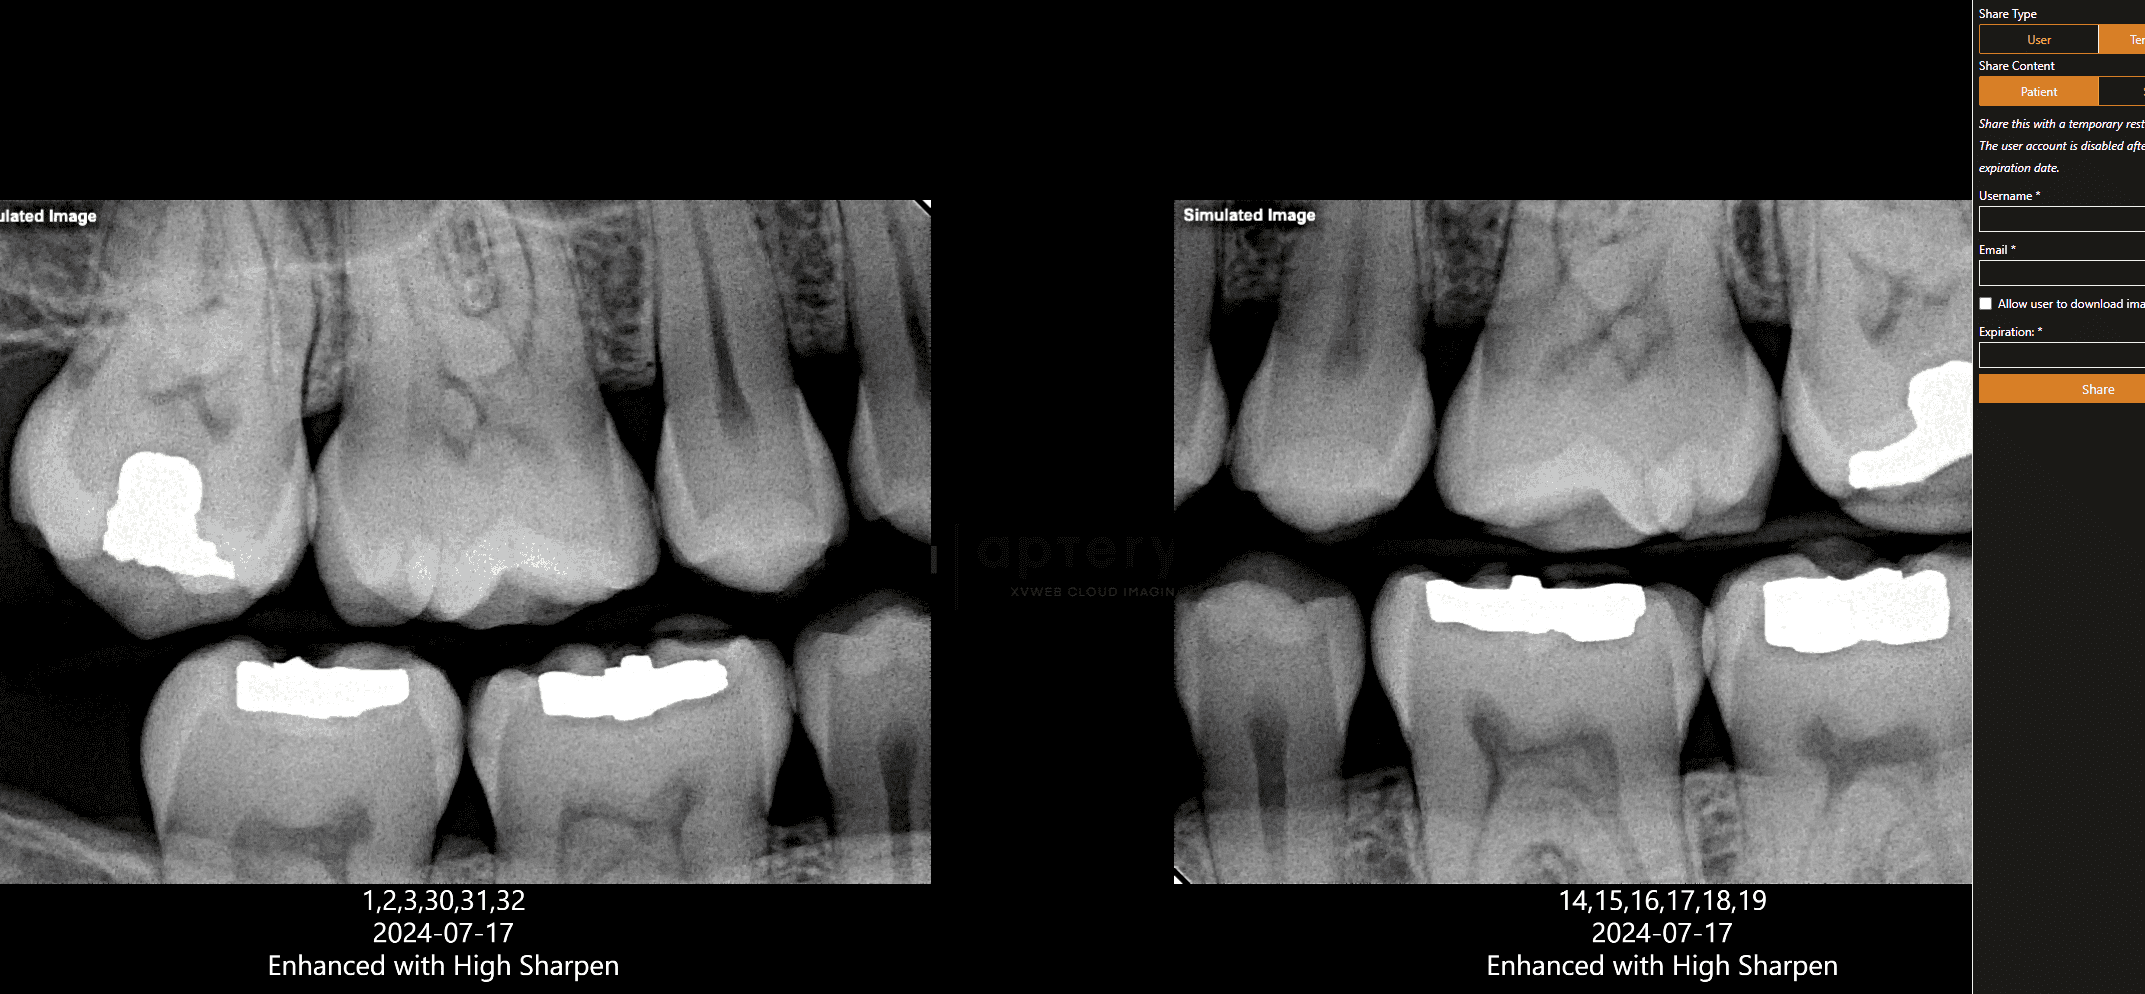

Apteryx XVWeb allows dental professionals to securely capture, store, and access X‑rays from anywhere. Apteryx is dental X-ray software built for practices seeking diagnostic accuracy, consistent imaging, and seamless integration with the devices they already use.

Capture, view, and analyze images in one place, from any device.

Leverage custom clinical filters and image enhancement tools, templates, bitewings, and measurement tools. Quickly detect untreated conditions with AI analysis.